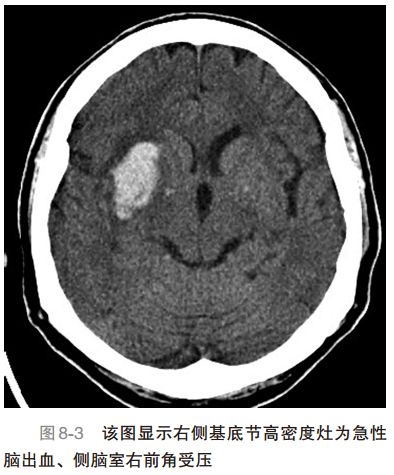

1. IS患者需溶栓或抗凝治疗,如在症状发作后3 ~ 4.5h(图 8-1和图8-2,缺血性脑卒中的头颅CT表现)。